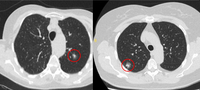

Computed tomography (CT) showing examples of malignant perifissural nodules. Note the spiculated edge of the nodules and the evident retraction of the adjacent fissure. Both resection tissue analyses confirmed adenocarcinoma of lung

From the collection of Dr George Tsaknis, MD, PhD, FRCP(London), MRQA, MAcadMEd, PGCert; used with permission